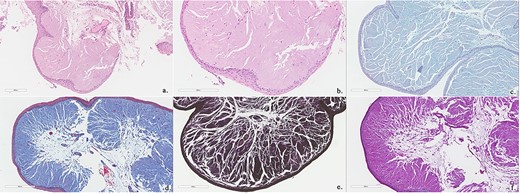

Histopathology showed abundant deposits of acellular amorphous hyaline material in the subepithelial stroma. This material was diastase-resistant Periodic acid–Schiff (PAS) positive, and stained with Alcian blue (pH 2.5) and Elastin van Gieson (EVG). It was negative for Congo Red (amyloid) and Trichrome stain (for fibrin). The overall features were consistent with LP (Fig. 4). No clinically relevant variants were identified in the ECM1 gene by sequence analysis. The patient was referred to internal medicine to rule out the systemic manifestations of the disease; their investigations were unremarkable. The patient was given the options of surgical and medical management; she preferred medical management. She was managed conservatively with an anti-reflux medication, oral corticosteroids for 14 days and postoperative voice rest instructions. She was reassessed 3 and 6 months postoperatively with stable laryngeal symptoms and resolved dysphagia and was given a yearly follow-up for reassessment.

Biopsies show polypoid squamous epithelium-lined stroma containing abundant amorphous, eosinophilic acellular hyaline material (Hematoxylin and Eosin stain; a, b). This material is Alcian blue positive (c), PASD positive (d), EVG positive (e) and Trichrome (for fibrin) negative (f).

Histopathological examination of mucocutaneous lesions is the ultimate approach for diagnosis [3]. Microscopic analysis of eosinophilic, PAS-positive, diastase-resistant material in the submucosal layer of the dermis is a hallmark of LP [5, 8]. Examination of skin biopsy specimens shows thickening of the basement membrane, dermo-epidermal junction, papillary dermis, adjacent capillaries and around adnexal epithelia [2, 13]. Our patient underwent laryngeal biopsies only, which showed abundant subepithelial deposits of acellular amorphous material, a consistent finding of LP [5]. Brain CT and magnetic resonance imaging studies may show calcifications in the hippocampus and temporal lobes in later stages of the disease [6, 8, 14].